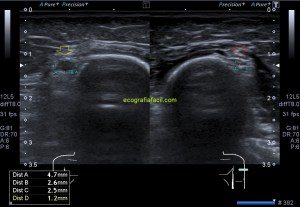

Paciente que acude derivado del traumatólogo por una sospecha rotura del extensor del pulgar. Cuando posicioné al paciente para iniciar la exploración y le hice el interrogatorio habitual, me contó que desde un traumatismo donde se rompió las dos muñecas, tiene una incapacidad para estirar completamente el dedo pulgar a la altura de la interfalángica, no de la metacarpofalángica.

1

Exploré el primer compartimento sin ningún tipo de novedad, tanto el Abductor Largo del Pulgar y Extensor Corto del Pulgar. Pasé al compartimento dos, Extensor Radial Largo del Carpo y Extensor Radial Corto del Carpo, ellos dos estaban sin novedad, pero este compartimento guarda una particularidad y una relación especial con el tercero, que es el del Extensor Largo del Pulgardel que está separado por tubérculo de lister, esta relación consiste en la coexistencia de los tres extensores y del paso superior o superficial que el extensor largo del pulgar realiza en un punto sobre el compartimento 2. Es importante que entiendas anatómicamente esta relación y te la enlazo aquí.

Lo que hace el tercer compartimento nada más desplazarnos hacia distal en el corte axial de la muñeca en su cara extensora y donde visualizamos el tubérculo distal separando ambos compartimentos 2 y 3, lo que hace el tercer compartimento, decía, es cruzarse por encima del dos para buscar diagonalmente su paso y su inserción en la cara dorsal del dedo pulgar. Si no entiendes esta anatomía, no vas a poder entender lo que pasa.

Lo que me llamó la atención fue que la parte superficial del segundo compartimento, correspondiente con el extensor largo del pulgar cruzando por encima del compartimento 2, era que estaba muy hipoecogénica y grande, así que una vez comprobado que los dos tendones del compartimento eran normales, y sabiendo que el tercero pasa por encima para cruzarse buscando el primer dedo, lo que hice fue seguir el tercer compartimento y lo que ví era que estaba situado en su lugar junto al tubérculo de lister, proximalmente, que a su cruce por encima del compartimento dos, estaba hipoecogénico y gordo y que ya en la mano, por donde cruza buscando el primer dedo, no estaba o al menos no estaba íntegro.

En este recorrido encontré un muñón, que se observa perfectamente en longitudinal, y que correspondía con el extensor largo del pulgar a la altura de su recorrido.

3

En esta imagen quiero que te fijes en el segundo compartimento y como el extensor largo del pulgar pasa por encima, los dos tendones del compartimento dos cortados en eje corto y el del tercero, cortado, pero en un corte para-axial. Lo importante es que te fijes en la ecogenicidad de ELP, en la izquierda hiperecogénico, isoecogénico con el segundo compartimento, por tanto normal. En la derecha hipoecogénico y más gordo, patológico.

4

Seguimos avanzando hacia distal, seguimos observando las mismas diferencias en las imágenes comparativas. Imagen justo antes de la rotura.

5

En la rotura el tendón es muy pequeño, pero normal en la izquierda y en la derecha lo es igual de pequeño, pero aplanado y con la pérdida de la ecogenicidad normal.

6

Después de la rotura, avanzando a distal, el tendón retraído, hipoecogénico, mucho más grande que su comparativo contralateral.

7

Corte en eje largo correspondiente a la imagen 6, donde se ve claramente lo que pasa y es definitivo para el diagnóstico final.

8

Comprobar con doppler para ver si hay actividad, que no la hay y es que la lesión no es reciente y esto podría explicar tal circunstancia.

En resumen, desde la imagen 3 a la 8 observas el recorrido ecográfico del tendón extensor del pulgar desde proximal hasta distal, pasando por el foco de rotura y terminando con el muñón en axial y en longitudinal según marcan los pictogramas.

La imposibilidad de poder extender el pulgar quedaba explicada con estos hallazgos. Un caso muy bonito, que espero que te sirva, sobre todo para que veas lo importante de la anatomía en esta técnica de la MSK.

Esta imagen final demuestra muy claramente lo que ha pasado y como ha quedado la zona en cuestión. El tendón retraído parece continuarse hacia proximal, filiforme, hasta que llega a otro ensanchamiento hipoecogénico, en relación con el muñón proximal.